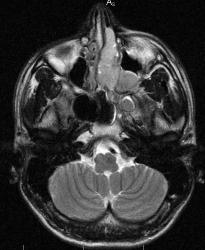

В последнее время на сайте много сообщений о патологии такой локализации. По закону парности и ко мне пришел пациент с направлением "Исключить опухоль орбиты". Мужчина 1982 г.р. жалуется на значительное снижение зрения на левый глаз. Зрачок расширен, движения глаза ограничены.

Похоже это образование (заболевание) исходит из решетчатого лабиринта или из основной пазухи ( жалко мало снимков и нет характеристик

контрастного усиления.